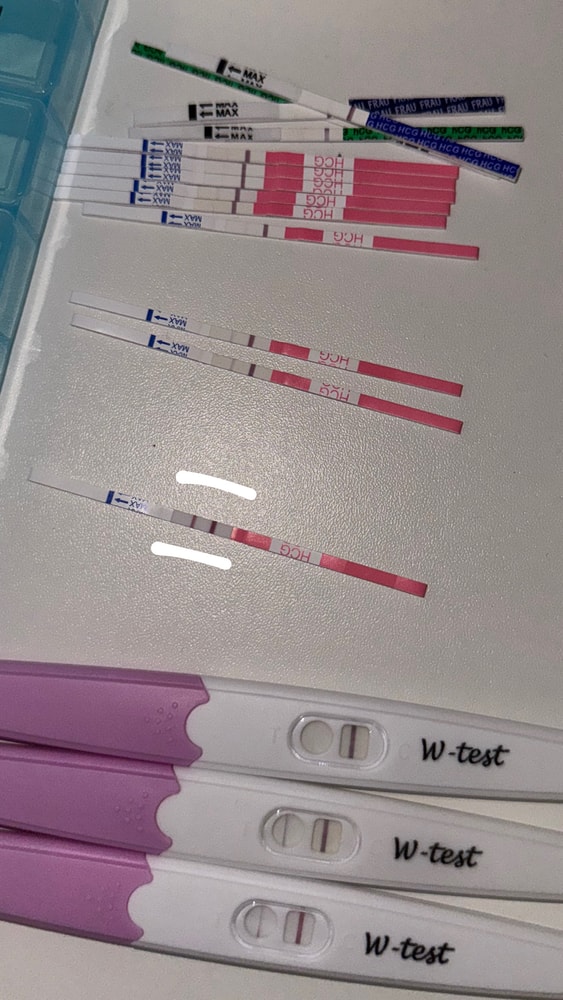

Сегодня 4 день задержки. Белым отмеченный тест сегодняшний(примерно в 11 утра проверяла) остальные до 30.10 проверенные. Примерно в 7 вечера заметила светло коричневые выделение в мааалом количестве. Сразу вызвали скорую. В больнице сначало осмотрели по узи. Написал есть подозрение на внематочную беременность с левой стороны. Но там мне не больно. Меня беспокоит только поясница чуток. Потом гинеколог на кресле осмотрела. Сказала что матка увеличена. На внематочную подозрении у меня нет, наверное в пути к матке сказала гинеколог. Акушерский срок 5н3д. Эмбриональный на 2 недели примерно меньше будет же. Что думаете?

Тесты полосят, значит, пя уже прикрепилось, на УЗИ пя видно же, не описывают, где оно?